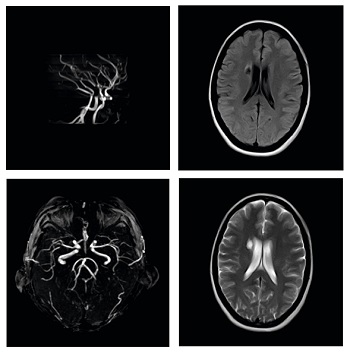

Es un sistema abierto de imán permanente de 0,5 T equipado con un potente sistema de gradientes y de RF. En combinación con la tecnología de imágenes avanzada, lo que lo convierte en un sistema de alta gama, es comparable a los sistemas de resonancia magnética de alto campo.